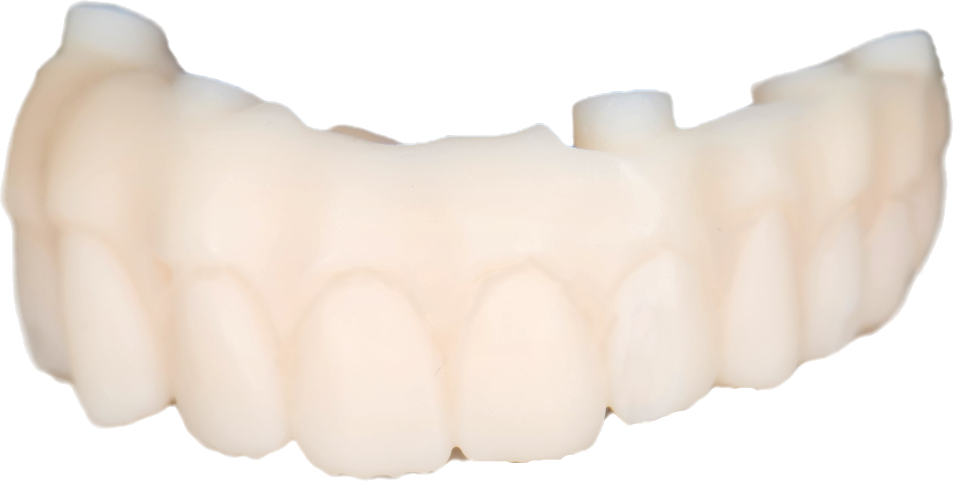

The scanned arch and implant position will be used to modify the waxup intaglio and cut out screw channels and direct to MUA connections.

For this procedure we chose the ROSEN Screw to be able to print a bridge and to not need to cement TiBases that would introduce and imprecision with every cement gap of every implant connection. Also with this screw a torque of only 10 N ( so basically hand screwed ) is necessary and because of the small space necessary to fit them in the design the walls of the preparation are far thicker then usual and this leads to less breakage in the temps.

After final design was achieved a Temporary bridge was printed out of definitive resin with the help of the Shining Accufab CEL ,then washed in the FabWash , individualized with the candy coat technique and post cured with the FabCure2 and in around one hour and thirty minutes from the scan was then delivered to the patient. This allows for same day All on X delivery.